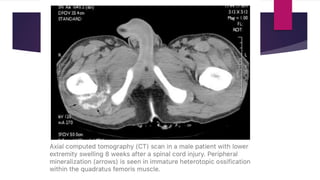

 CT scan – Reveals zonal phenomenon with a rim of calcification of

varying thickness at periphery while central area similar to muscle.

 Intermediate stage(consolidation phase)  Lesion becomes firm with constant pain.  Limitation of movement at adjacent joint if large.  Radiograph – “Dotted veil” calcification (confusing with rhabdomyosarcoma or synovial sarcoma). There may be continuous or discontinuous peripheral calcification.  CT scan – Reveals zonal phenomenon with a rim of calcification of varying thickness at periphery while central area similar to muscle.  MRI – more nonspecific with variable signal at center and decreased signal intensity at periphery on all pulses.  Calcific tendinitis is d/d at this stage